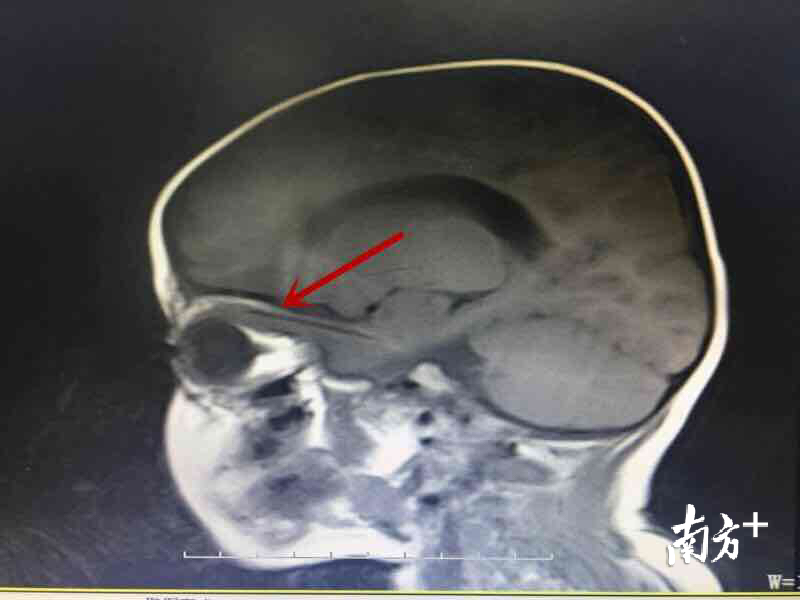

“影像检查结果显示,孩子颅内有一根挺长的异物。应该是从眼睑进去,穿过了眼眶,避开了视神经跟眼球,大部分进入了脑子里面了。” 陈镇洲表示,患儿受伤已近一个月,他的母亲并不知道受伤当时的情况,更不清楚异物是什么。

当时,患儿眼底水肿,一侧瞳孔已有散大,异物不仅已刺入颅内,而且与脑内的主血管只有一毫米的距离。“如果不尽快取出异物,清除脓液,患儿有失明、颅内脓肿形成乃至生命危险”,陈镇洲表示。

6厘米长的异物从伊力哈木江的眼眶插入,进入脑颅,这场景孩子妈妈想都不敢想,也让广东援疆医疗专家陈镇洲和李星仪觉得棘手。从影像检查结果来看,异物并不大,已经进入颅内,拉出来恐怕会有伤及神经、血管,只能开颅。而孩子太小了,手术不仅要成功,还要让创伤尽可能小。

为了最大程度减少对患儿容貌的影响,陈镇洲手术取了一个5厘米的小切口,术中才发现异物为小树枝。陈镇洲解释,“异物旁边的两根血管一旦破掉,患儿可能就会有生命危险的。因为树枝尾端已深入眼眶内2厘米,并刺入脑子里面,我们没有办法通过眼眶抽出来,只能是先把木棍夹碎剪断,然后再分块取出来。”